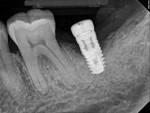

A 64-year-old female patient experienced early loss of attachment due to peri-implantitis as seen in a July 2012 periapical radiograph of an implant placed at the No. 18 site (Figure 1). Fifteen months later examination revealed marked progression of attachment loss and increase in probing depth (Figure 2).